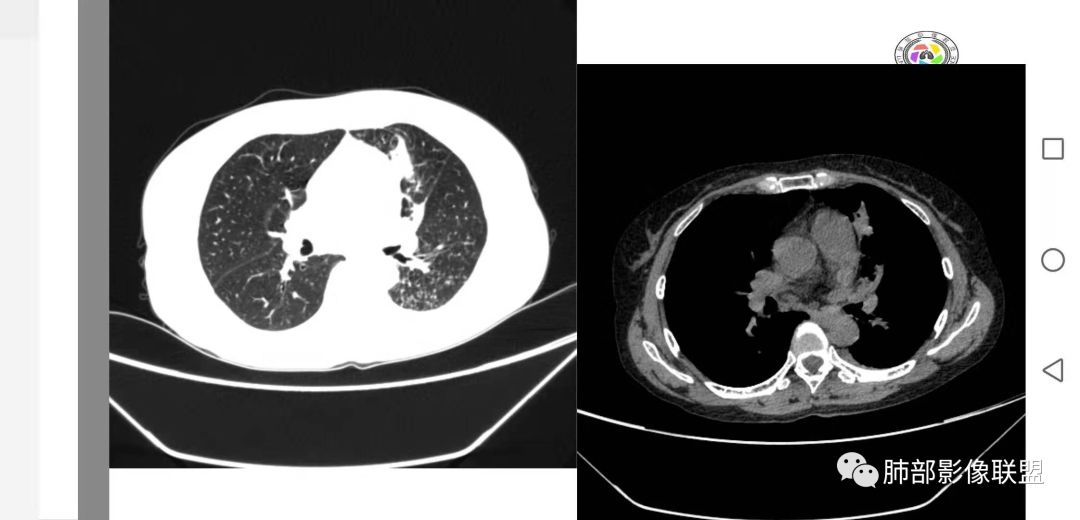

左肺团块影,形态不规则,其内见充气支气管征,增强扫描明显强化,其内见液化坏死区。下叶基底段见斑点状密度增高影。双肺门见斑点状钙化影。疾病谱有结核,增强除外了。肺癌和淋巴瘤鉴别。

病灶远端有扩张支气管,树芽,实变,纵隔肺内淋巴结钙化,考虑肺结核。

强化不是很明显,我考虑炎性病变,结核放第一位。

支气管是通畅的

@甄德强 庆安县人民医院 影像科? 增强强化,排除了,强化不符合。一般结核都是薄环形强化吧?这个病灶边缘及肺内太干净,结核一般很少这样

纵隔还有钙化淋巴结

支气管狭窄后扩张是炎性特点

下叶背段有树芽

左肺占位,边界平直,无明显膨胀性,炎性首先考虑,支气管壁不光滑,考虑气道来源,青年女性,有地热,乏力,体重减轻,结合病灶周围有树芽征,我考虑结核!

整个上叶尖后段阻塞性肺不张的表现,从强化来看没有异常结节状或肿块样强化,肿块内部点状钙化、纵隔多发小淋巴结、下叶背段有树芽征,整体来看支持肺结核,让人不放心的是最后一幅冠状位重建的图像尖后段支气管堵了,而且有轻度的隆起,所以很难除外粘液表皮样癌(女性,鳞癌可能性小),如果是我写报告肯定会建议纤支镜检查

中年女性,反复咳嗽咳痰4月,加重半月,咳嗽,咳黄痰。胸CT:左肺体积缩小,左肺上叶病变,病灶内可见支气管征,病灶边缘可见棘突样改变,病灶周围可见结节状卫星灶,纵隔可见淋巴结肿大,部分淋巴结可见钙化灶。增强CT病灶内可见低密度坏死区,冠状位病灶内支气管可见扩张,病灶整体呈收缩,考虑患者为良性慢性感染性病变,结核?放线?,建议支气管镜检查。

考虑结核伴混合感染。中青年女性,持续低热、不正规抗感染症状加重。左上肺低密度肿块,左上固有段支气管未显影(结核侵蚀干酪样坏死),左上舌段支气管通畅但增厚变形。左下肺树芽征新发支气管播散。鉴别:粘液腺癌

左上叶实变不张,膨胀生长,上叶开口阻塞?,病灶内支气管扩张,明显延迟强化,内见低密度灶及点状钙化,周边见小叶间隔增厚丶结节,右斜裂结节

中年女性,反复咳嗽咳痰4月。胸CT:左肺上叶块状病变,病灶内可见支气管征,边缘见棘突样改变,周围可见结节状卫星灶,纵隔可见淋巴结肿大,部分淋巴结可见钙化灶。增强CT病灶内可见低密度坏死区。病灶整体呈收缩,考虑为良性病变,结核可能性大,建议支气管镜检查。